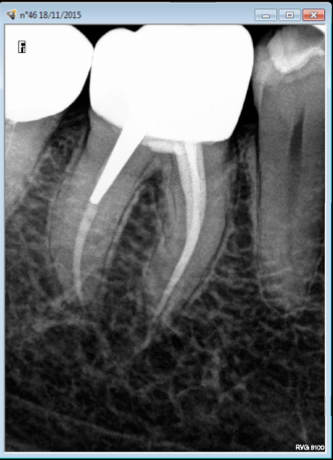

Ca par contre c'est normal. Pano fait dans un autre cabinet et soins aussi. Carie 46 pas de douleur et ......magie une endo IC coiffe en moins de temps qu'il ne faut pour le dire, patient solvabilisé dent défoncée. On a échappé à la peinture canalaire, ouf ! -)))))